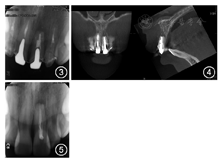

根管中部以上可见高密度桩核影像,根充欠填,

根尖有外吸收,根尖周低密度影。

根管中上段无明显显影,结合临床检查判断为纤维桩,根充欠填,根尖周未见明显低密度影(图3)。锥形束CT显示

根尖约4 mm×3 mm透影区,根尖部唇侧骨板缺损。

根尖可见约1 mm×2 mm透影区,唇侧骨板完整(图4)。

根尖未见明显低密度影。1年前根尖X线片显示

根充欠填,根尖低密度影,

牙冠完整,根尖无异常(图5)。